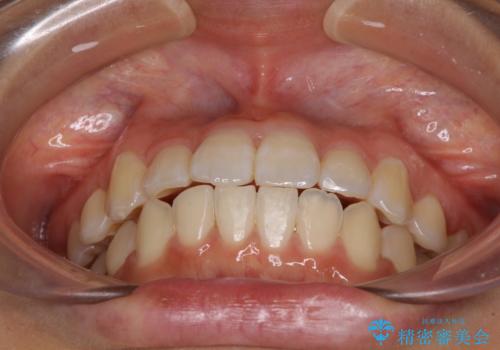

- 上下のデコボコと前歯のクロスバイトを改善したいとのことで来院された患者様です。

極力短期間で治療したいとのことで、ワイヤー装置による矯正治療を行うこととしました。

お住まいが遠方であったため、マウスピースによる矯正治療も提案しましたが、ご自身でのマウスピースの管理の面倒くささと、なるべく早く治療を終えたいとのことで、ワイヤー矯正を選択されました。